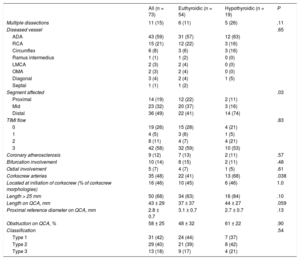

RESULTSThe study included 73 consecutive patients with SCAD; 26% of them were classified as having hypothyroidism. Most patients with SCAD were women (77%; n = 56), Caucasian, and with relatively few cardiovascular risk factors. The differences in the baseline characteristics of patients with SCAD according to their thyroid status are shown in Table 1. Most patients with SCAD and hypothyroidism received thyroid hormone replacement therapy (74%, n = 14) and maintained good metabolic control (86%, n = 12). Antithyroid antibodies were elevated in 16% (n = 3). All hypothyroid patients with SCAD were female (100% vs 69%; P = .01), with a nonsignificant tendency for higher prevalences of FMD (36% [4/11] vs 24% [7/29]; P = .43) and dyslipidemia (58% [n = 11] vs 35% [n = 24]; P = .09) vs euthyroid patients. In all patients, the form of presentation was ACS (Table 1). The angiographic characteristics of the 2 groups are compared in Table 2. Most patients had a single long (> 25mm) type 1 or 2 dissection located in the anterior descending artery and in distal coronary segments. SCAD patients with hypothyroidism had a higher frequency of distal vessel involvement (74% [n = 14] vs 41% [n = 22]; P = .03) and tended to show a more diffuse involvement (84% [n = 16] vs 63% [n = 34]; P = .1). Via quantitative coronary angiography measurement, the vessels of patients with SCAD tended to be smaller (mean proximal reference diameter on quantitative coronary angiography, 2.7 ± 0.7mm vs 3.1 ± 0.7mm; P = .13) and with more diffuse involvement (length on quantitative coronary angiography, 44 ± 27mm vs 37 ± 37mm; P = .059).

Angiographic Characteristics of the Spontaneous Coronary Artery Dissection Group

| All (n = 73) | Euthyroidic (n = 54) | Hypothyroidic (n = 19) | P | |

|---|---|---|---|---|

| Multiple dissections | 11 (15) | 6 (11) | 5 (26) | .11 |

| Diseased vessel | .65 | |||

| ADA | 43 (59) | 31 (57) | 12 (63) | |

| RCA | 15 (21) | 12 (22) | 3 (16) | |

| Circumflex | 6 (8) | 3 (6) | 3 (16) | |

| Ramus intermedius | 1 (1) | 1 (2) | 0 (0) | |

| LMCA | 2 (3) | 2 (4) | 0 (0) | |

| OMA | 2 (3) | 2 (4) | 0 (0) | |

| Diagonal | 3 (4) | 2 (4) | 1 (5) | |

| Septal | 1 (1) | 1 (2) | ||

| Segment affected | .03 | |||

| Proximal | 14 (19) | 12 (22) | 2 (11) | |

| Mid | 23 (32) | 20 (37) | 3 (16) | |

| Distal | 36 (49) | 22 (41) | 14 (74) | |

| TIMI flow | .83 | |||

| 0 | 19 (26) | 15 (28) | 4 (21) | |

| 1 | 4 (5) | 3 (6) | 1 (5) | |

| 2 | 8 (11) | 4 (7) | 4 (21) | |

| 3 | 42 (58) | 32 (59) | 10 (53) | |

| Coronary atherosclerosis | 9 (12) | 7 (13) | 2 (11) | .57 |

| Bifurcation involvement | 10 (14) | 8 (15) | 2 (11) | .48 |

| Ostial involvement | 5 (7) | 4 (7) | 1 (5) | .61 |

| Corkscrew arteries | 35 (48) | 22 (41) | 13 (68) | .038 |

| Located at initiation of corkscrew (% of corkscrew morphologies) | 16 (46) | 10 (45) | 6 (46) | 1.0 |

| Length > 25 mm | 50 (68) | 34 (63) | 16 (84) | .10 |

| Length on QCA, mm | 43 ± 29 | 37 ± 37 | 44 ± 27 | .059 |

| Proximal reference diameter on QCA, mm | 2.8 ± 0.7 | 3.1 ± 0.7 | 2.7 ± 0.7 | .13 |

| Obstruction on QCA, % | 58 ± 25 | 48 ± 32 | 61 ± 22 | .90 |

| Classification | .54 | |||

| Type 1 | 31 (42) | 24 (44) | 7 (37) | |

| Type 2 | 29 (40) | 21 (39) | 8 (42) | |

| Type 3 | 13 (18) | 9 (17) | 4 (21) | |

ADA, anterior descending artery; LMCA, left main coronary artery; OMA, obtuse marginal artery; QCA, quantitative coronary angiography; RCA, right coronary artery; TIMI, Thrombolysis In Myocardial Infarction.

Values represent No. (%) or mean ± standard deviation.

Half of the patients had”corkscrew“coronary arteries and, in half of these arteries, the dissections began at the beginning of the first curvature of the vessel (Table 2). The group with hypothyroidism showed a higher prevalence of arteries with corkscrew morphology (68% [n = 13] vs 41% [n = 22]; P = .038). In 2 patients, both with hypothyroidism, the diagnostic catheter caused an iatrogenic coronary artery dissection in apparently healthy proximal segments of the same artery that had a distal SCAD.